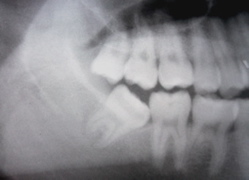

症例1

これは親知らずではありせんが、写真上からも「絶対に抜歯」と判断されました。なんとか保存を、、、と望む気持ちも分かりますが、プロである我々が「ダメ」と判断したものを無理に残しても良いことはありません。

実際に抜いてみると、根の周りに歯石が付着しているのが確認できます。根の先端までこんなに真っ黒なのです。保存できるわけがありません。